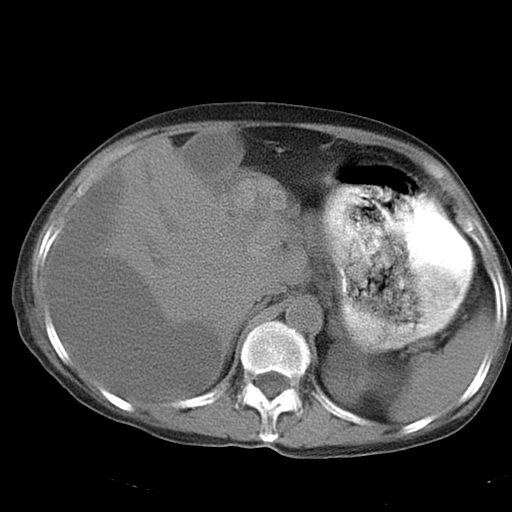

以下是引用dyqct在2006-12-7 21:08:00的发言:[br]考虑:1、肝内外胆管多发性结石伴肝左叶外侧段肝萎缩;[br] 2、右膈下多发脓肿;[br] 3、右侧少量胸腔积液、斜裂积液;[br] 4、左肾囊肿。

以下是引用jiazh在2006-12-7 20:37:00的发言:[br]肝脏周围半狐形低密度影,肝脏表面受压推移,考虑膈下脓肿可能性大;2、右侧胸腔积液

以下是引用拾荒者在2006-12-7 21:44:00的发言:[br]肝内外胆管多发结石,右膈下多发脓肿,右胸膜腔及叶间裂积液,左肾囊肿。[br] [br]